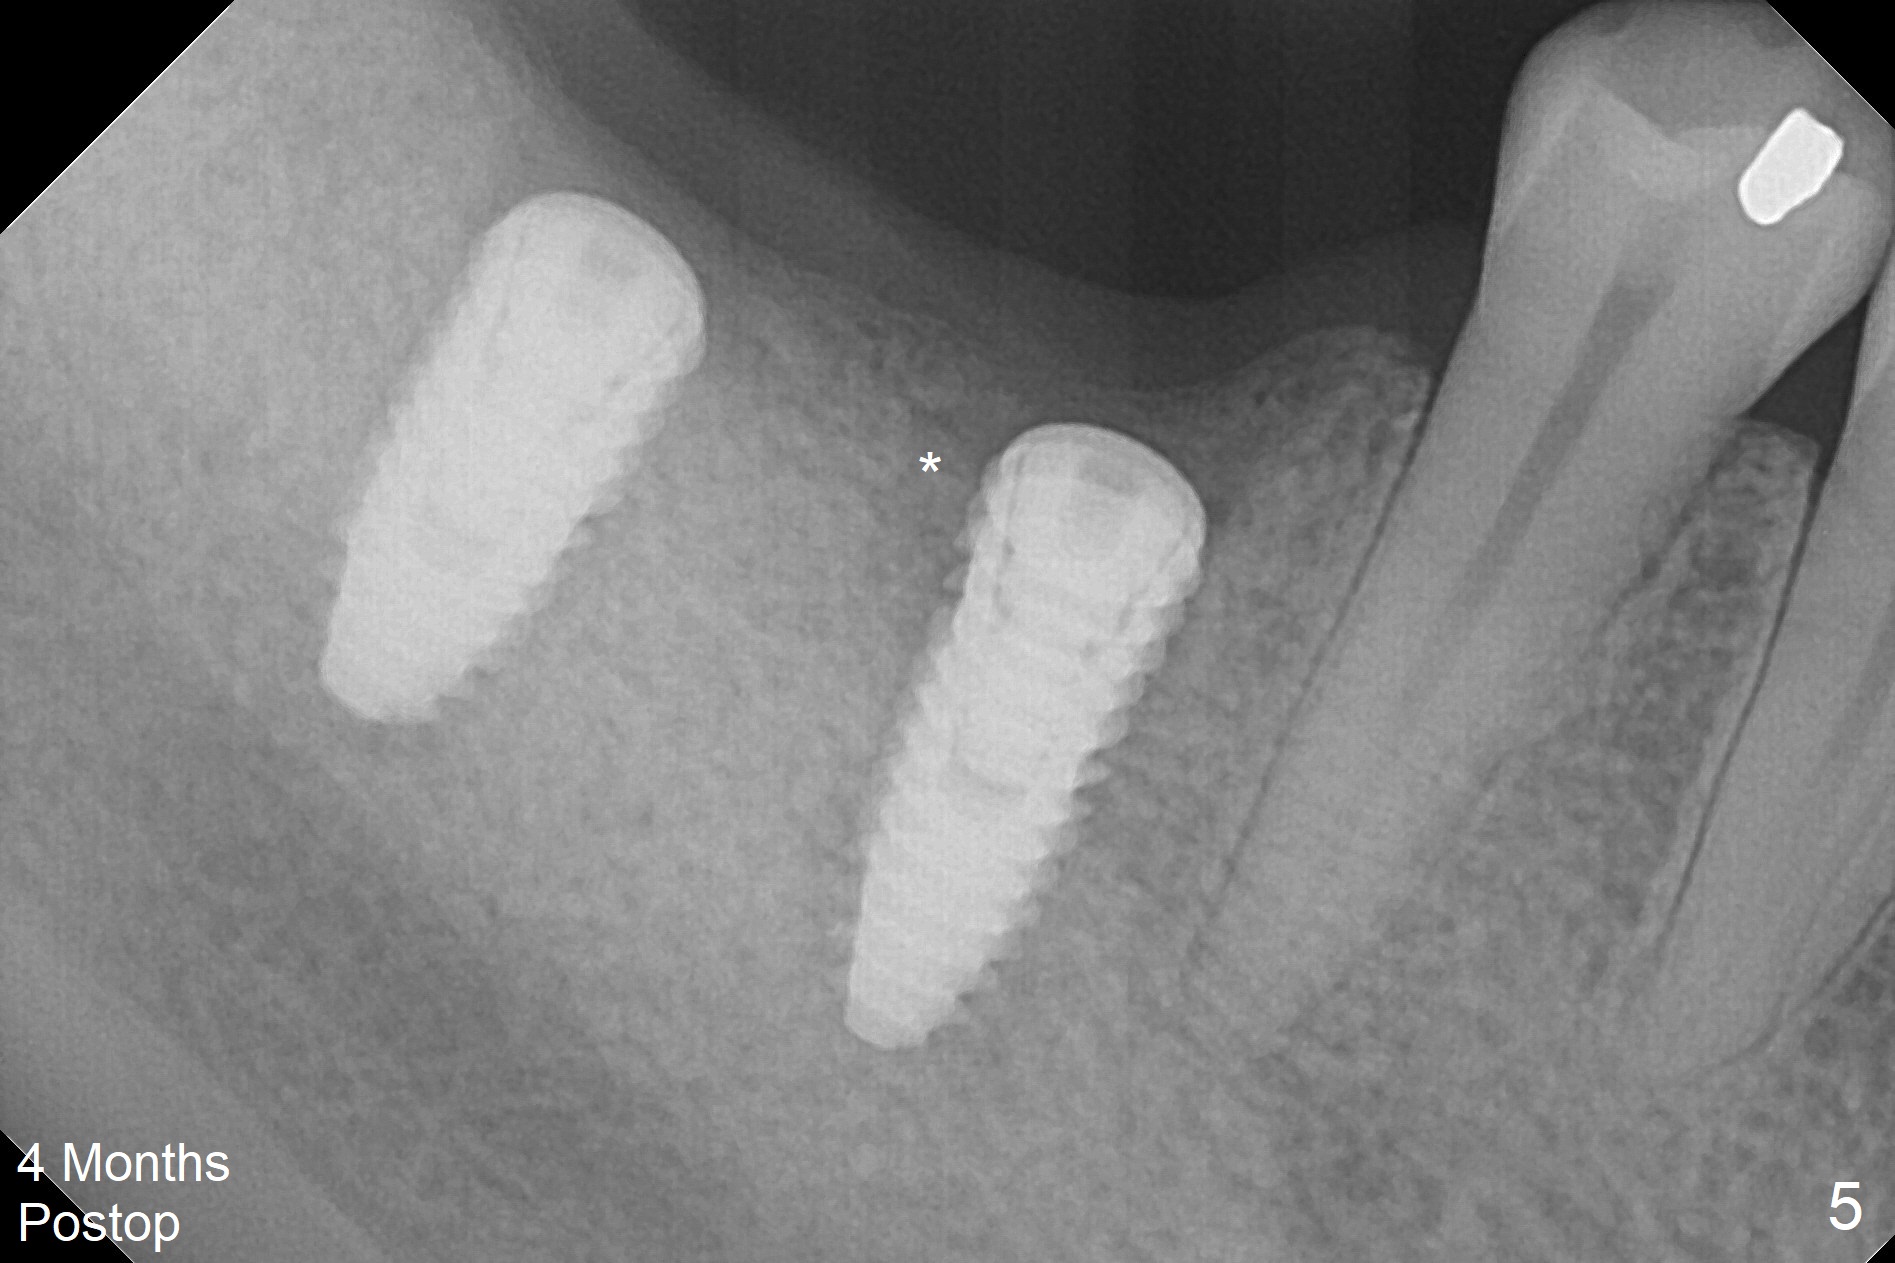

Infection is not so typical.  There is no recent postop X-ray, just 18-19 days postop.   Thanks for the reply.  We will keep watching.  The healing abutments, loose and associated with gingival inflammation, are removed 2.5 months postop (Fig.4).  There is crestal bone resorption, although the implants are stable.  The crestal bone resorption persists especially #30 distal 4 months postop (Fig.5 *).  When the implants are uncovered, there is mild bone loss distobuccal to #30 implant, consistent with early periimplantitis.  Bone graft is placed after debridement and healing abutment placement.  There appears no bone loss nearly 9 months postop (Fig.6).  The soft tissue looks healthy.  Cementation abutments (5.7x4(3) and 5.7x4.5(3) mm at #30,31, respectively) are placed for impression.  The distobuccal gingiva at #30 is hyerplastic 10 months postop (Fig.7 *, immediately before cementation), which is consistent with bone loss (Fig.8,9 * (periimplantitis)).  It is hoped that the infection will dissolve with improved oral hygiene (water pik) over the smooth final restoration.  In fact it is, i.e., the implants at #30 and 31 remain asymptomatic with the healthy gingiva 6 months post cementation (Fig.10,11).  There is mild crestal bone loss at #30 and 31 ten months post cementation (Fig.12).  Crown/implant ratio is the basis for screw loosening.  In fact the crown/abutment at #30 is loose 4 months later.  Incomplete seating of the abutment may be a culprit (Fig.12).  The gingival cuff is not healthy; a 6.8x7 mm healing abutment is placed with gingival blanching with Cetacaine and antibiotic ointment.  Next visit place a new smaller diameter abutment (4.5 or 5.2) with probably longer cuff (4 mm) or the existing abutment with no proximal contact crown, torque 25-30 Ncm and take BW with sensor 2 or PA with sensor 1.  In fact there is resistance to hand tighten a 4.5x4(4) mm healing abutment, which is due to contact with the mesial crest (Fig.13 *).  After use of 5.5 and 6.0 mm profile drills, the 6.8x7 mm healing abutment is reseated.  The latter appears to contact the mesial crest (Fig.14).  Later a 6x5 mm healing abutment is placed.  New crowns with new abutments are delivered 2 years 3 months postop (post Coronavirus lockdown).